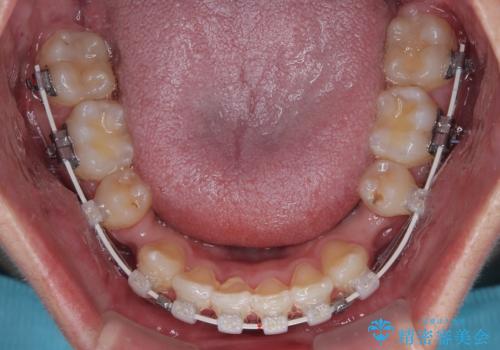

- 矯正装置

- 審美装置

- 今回ご紹介するのは、

「全体的なデコボコ(叢生)」「上下の正中のずれ」 を主訴として来院された20代男性の患者様の症例です。

叢生が強く、歯が並ぶスペースが不足していたため、

上下左右の第一小臼歯を抜歯して、矯正治療のための適切なスペースを確保する計画としました。